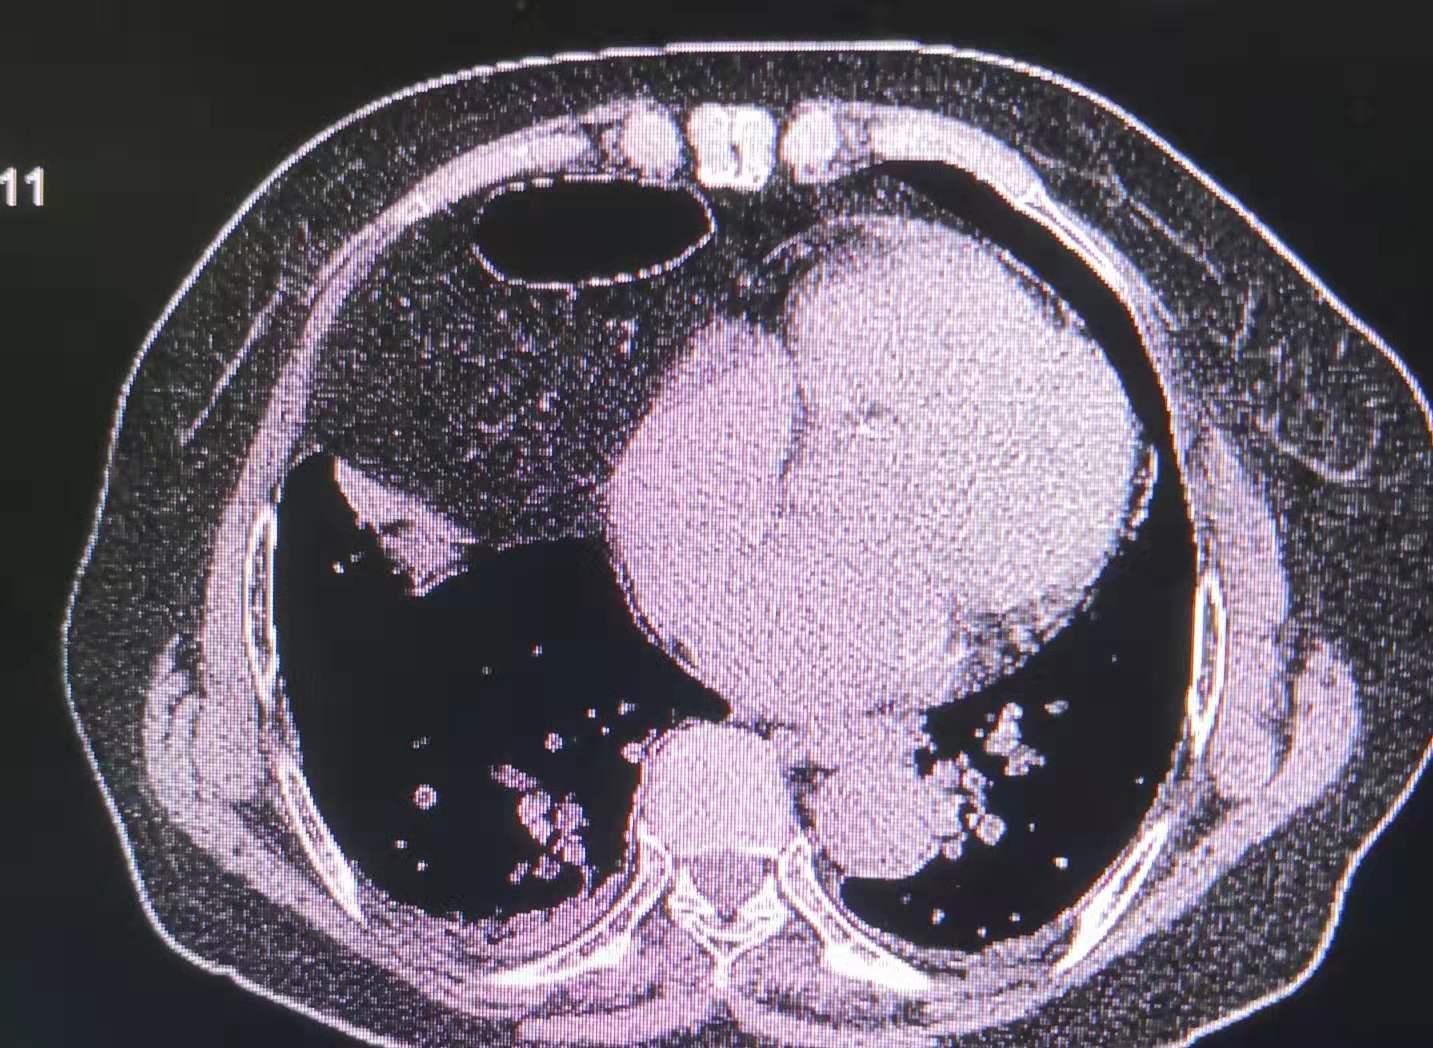

针对胸部的脂肪瘤,我院设备强大 的再重建功能显示,患者的膈肌上的巨大肿块影中有奇怪的积气现象。

往下追查,看到肿块来源于腹部,其中奇怪的气体影,是腹部的肠管。

最后的结论是腹部肠管及肠系膜疝入胸腔,患者长期的消化不良的现象得到了解释。